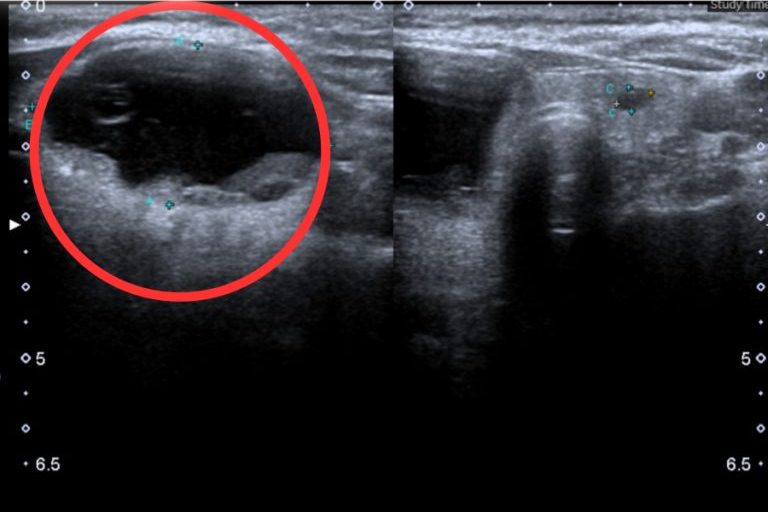

Hình ảnh siêu âm tuyến giáp. Ảnh: BVCC

Kết quả siêu âm tuyến giáp cho thấy thùy phải – eo và thùy trái của người bệnh có cấu trúc dạng đặc và nang với kích thước 42mm x 23mm và 3.4mm x 5.1mm. Người bệnh được chẩn đoán nang giáp hai thùy và eo Tirads 1 (mô giáp lành), sau khi hội chẩn, các bác sĩ quyết định lựa chọn phương án phẫu thuật nội soi cắt bán phần thùy phải và eo giáp qua đường nách – ngực bằng dao cắt siêu âm.